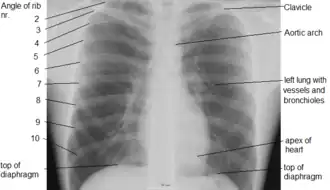

Landmarks

In the average person, the diaphragm should be intersected by the 5th to 7th anterior ribs at the mid-clavicular line, and 9 to 10 posterior ribs should be viewable on a normal PA inspiratory film. An increase in the number of viewable ribs implies hyperinflation, as can occur, for example, with obstructive lung disease or foreign body aspiration. A decrease implies hypoventilation, as can occur with restrictive lung disease, pleural effusions or atelectasis. Underexpansion can also cause interstitial markings due to parenchymal crowding, which can mimic the appearance of interstitial lung disease. Enlargement of the right descending pulmonary artery can indirectly reflect changes of pulmonary hypertension, with a size greater than 16 mm abnormal in men and 15 mm in women.[6]

Appropriate penetration of the film can be assessed by faint visualization of the thoracic spines and lung markings behind the heart. The right diaphragm is usually higher than the left, with the liver being situated beneath it in the abdomen. The minor fissure can sometimes be seen on the right as a thin horizontal line at the level of the fifth or sixth rib. Splaying of the carina can also suggest a tumor or process in the middle mediastinum or enlargement of the left atrium, with a normal angle of approximately 60 degrees. The right paratracheal stripe is also important to assess, as it can reflect a process in the posterior mediastinum, in particular the spine or paraspinal soft tissues; normally it should measure 3 mm or less. The left paratracheal stripe is more variable and only seen in 25% of normal patients on posteroanterior views.[7]

Localization of lesions or inflammatory and infectious processes can be difficult to discern on chest radiograph, but can be inferred by silhouetting and the hilum overlay sign with adjacent structures. If either hemidiaphragm is blurred, for example, this suggests the lesion to be from the corresponding lower lobe. If the right heart border is blurred, than the pathology is likely in the right middle lobe, though a cavum deformity can also blur the right heard border due to indentation of the adjacent sternum. If the left heart border is blurred, this implies a process at the lingula.[8]